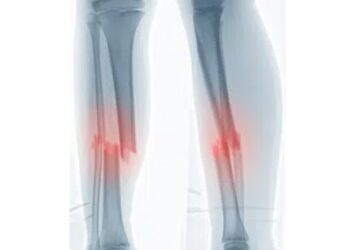

LireFracture spiroïde de la fibula : de quoi souffre exactement Casquette Verte ? Sur l’Arc of ...

LireCasquette Verte : fracture confirmée et arrêt forcé après l’Arc of Attrition. LE LIVRE DE CASQUETTE ...

LireContrairement à une fracture classique, secondaire soit à un remaniement de la structure osseuse (déminéralisation ou ...